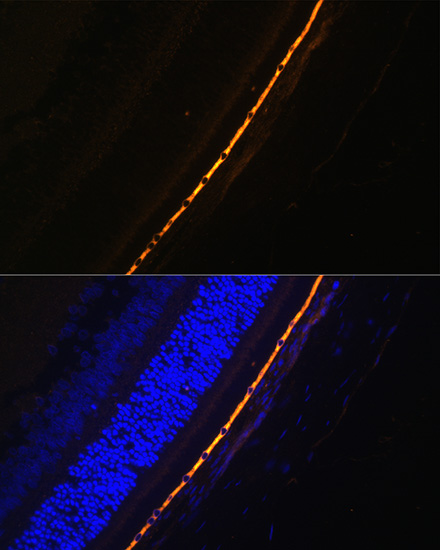

Immunofluorescence analysis of Rat eye cells using RPE65 at dilution of 1:100. Blue: DAPI for nuclear staining.

Immunofluorescence analysis of Mouse eye cells using RPE65 at dilution of 1:100. Blue: DAPI for nuclear staining.